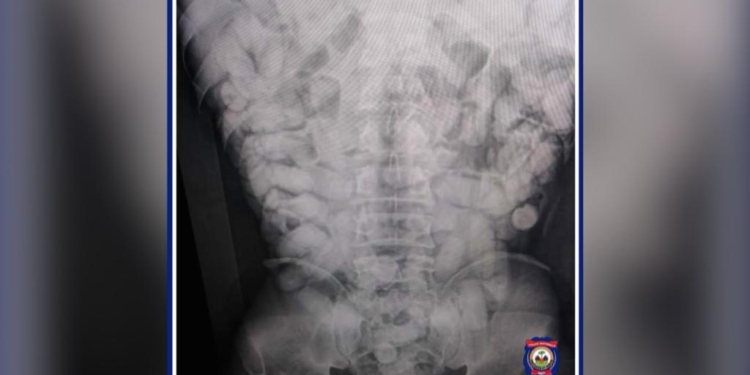

Suspecté de transporter dans son abdomen des corps étranges, l’individu qui se trouvait à bord d’un vol en direction de Paris a été conduit à l’hôpital Bernard Mevs pour des examens plus poussé.

À la suite d’une radiographie révélant la présence de corps étranger s’apparentant à de la drogue une procédure de récupération de ces corps a été entamée.

Le constat fait état d’un total de 1,35 Kg de cocaïne divisée en 102 bâtonnets de drogue récupérés dans l’intestin du nommé IK EGBOR.